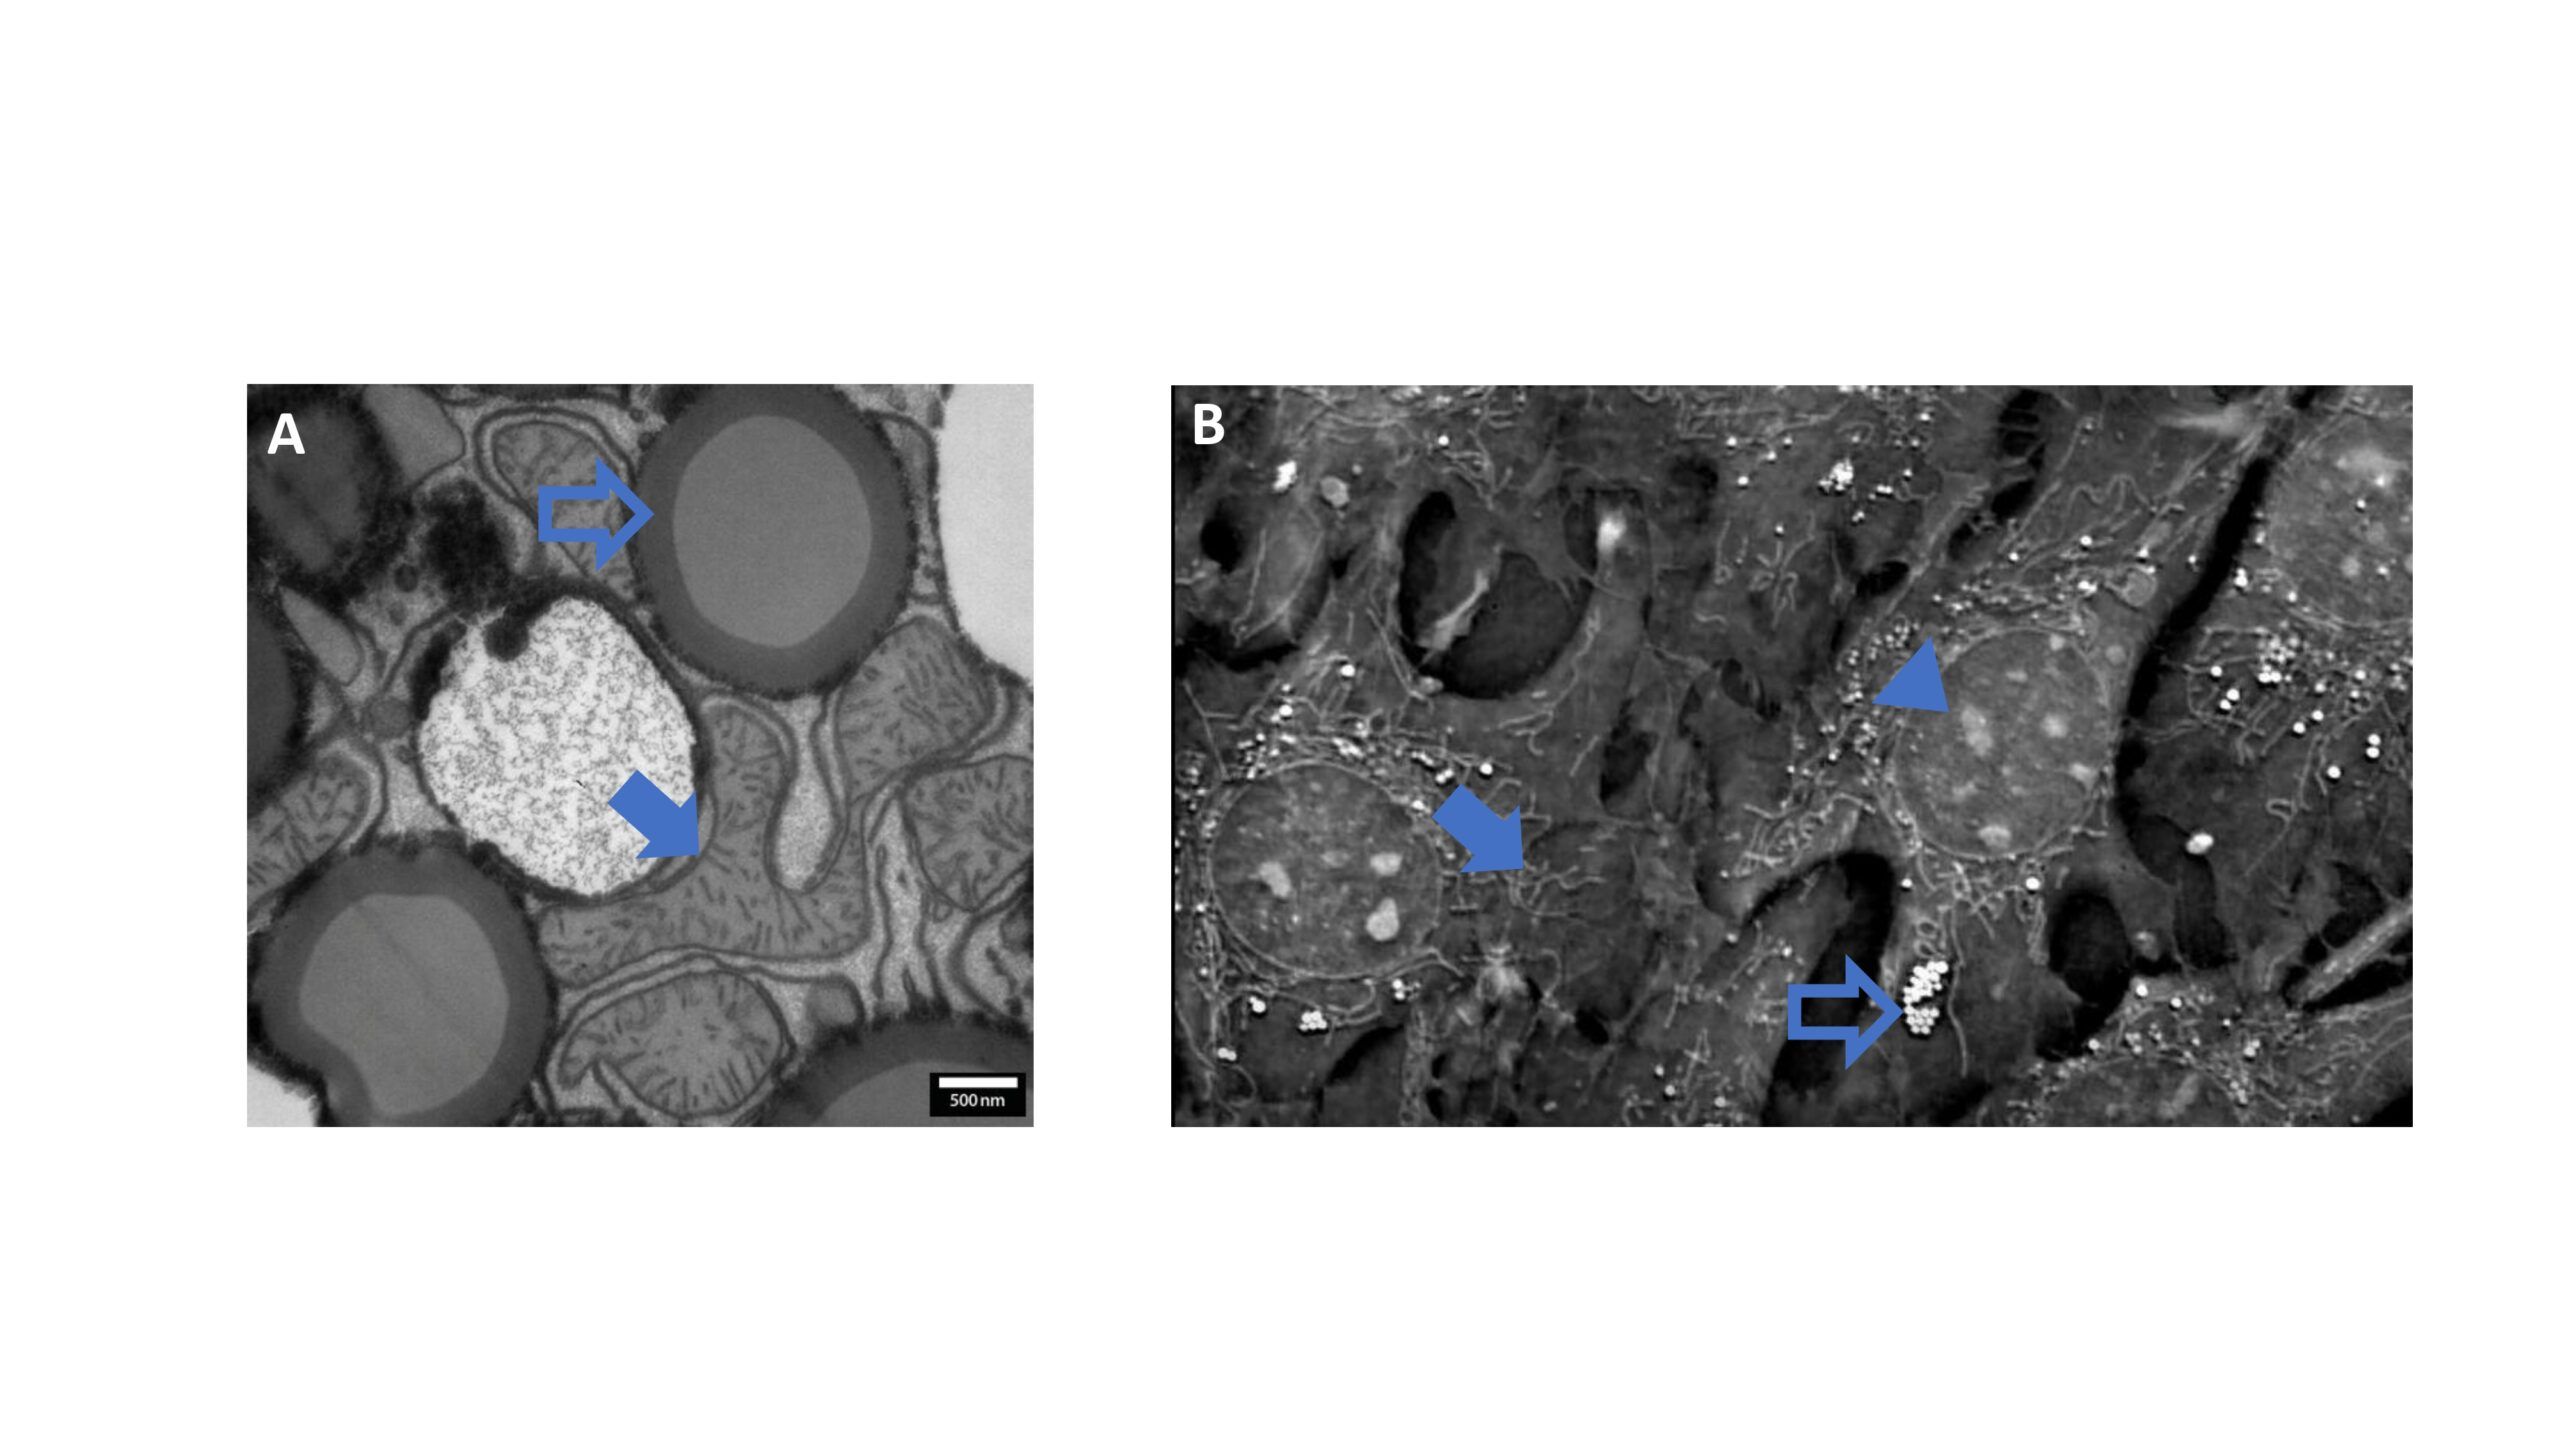

Application Note – Metabolismo Cellulare_page-0001